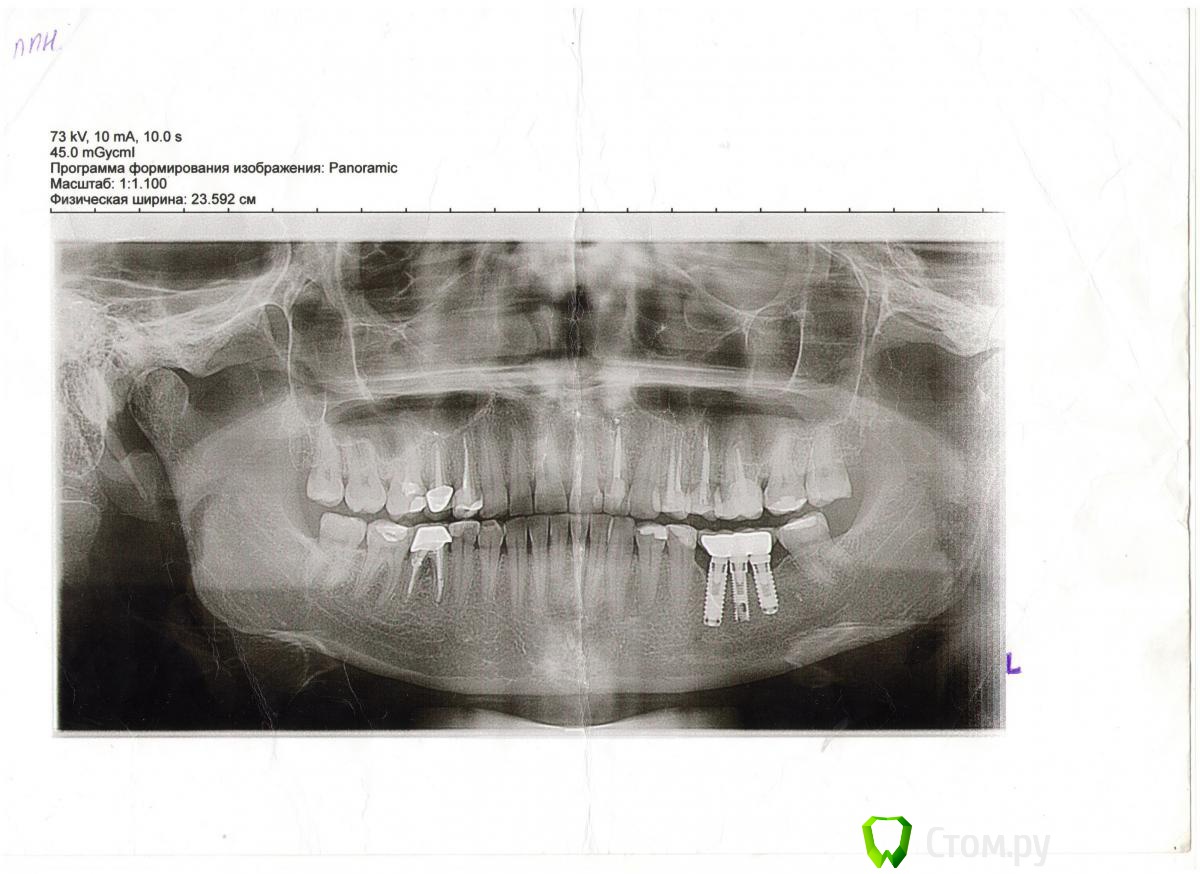

olesya.1211 Опубликовано 5 апреля, 2014 Автор Поделиться Опубликовано 5 апреля, 2014 А Вы какой зуб имеете ввиду? 22й ?Как давно его лечили(перелечивали)? А Вы какой зуб имеете ввиду? 22й ?Как давно его лечили(перелечивали)?22 й зуб. Кисту в нем я лечили в 2006 году методом депофореза, лечение прошло успешно, костная ткань наросла и на снимке все было отлично. Пол года назад (снимок 1) тоже вроде было без изменений. А в прошлом месяце я сделала ортопонограмму (снимок 2), делала его для консультации хирурга по поводу предстоящей имплантации, и хирург заметил, что над 22м зубом есть затемнение, сказал, что киста дала рецидив и лечить необходимо хирургически (резекция верхушки корня). В другой клинике предложили пролечить терапевтически с применением лазера. Вот я и не знаю каким методом лучше перелечить кисту. Подскажите, пожалуйста, какой метод лечения будет более надежный? Ссылка на комментарий

olesya.1211 Опубликовано 7 апреля, 2014 Автор Поделиться Опубликовано 7 апреля, 2014 К сожалению, снимка до лечения у меня нет. Знаю, что изначально, киста образовалась из-за неправильного лечения, так как пролечив зуб, спустя какое-то время он внезапно разболелся, тогда врач на снимке и обнаружила кисту, помню, что сказала, что киста довольно таки большая и предложила лечение депофорезом, но без гарантии. Сейчас по сравнению с прошлым годом (снимок 1) киста увеличилась (снимок 2), пока не болит. Ссылка на комментарий